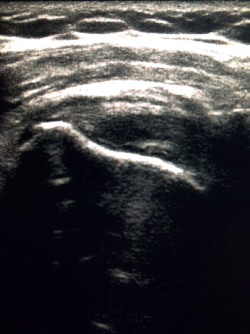

Figure 2. Ultrasound view of the long axis of the tendon of the supraspinatus muscle.

To ensure good ultrasound assessment of the posterosuperior cuff (Figure 2), we instruct the patient to place his or her arm behind the back, with the hand trying to touch the lower vertex of the scapula (Crass position). If the patient is unable to reach or keep this position during the exploration, he or she should be instructed to place the palm of the hand on the ipsilateral anterosuperior iliac crest with the elbow flexed (modification of the Crass position or Middleton position)(25). It is important to explore the tendon to its most anterior margin, as this is a frequent location of symptomatic lesions. For this purpose, in some cases the elbow must be displaced backwards, eliminating the last degrees of internal rotation.